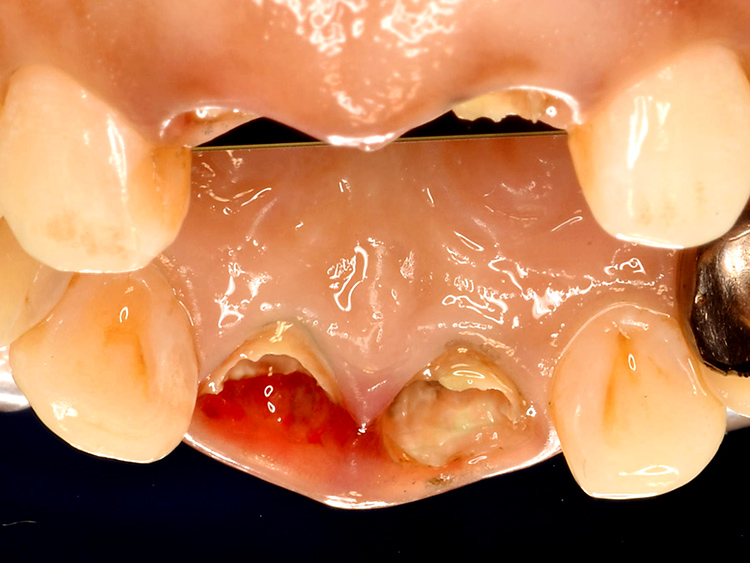

歯根破折部に隣接する歯肉は、赤く炎症を起こし損傷していました。

歯肉の健全な厚みや歯根への付着が失われ、細菌感染に対するバリア機能も低下していました。せっかく歯を保存し修復できたとしても、その後に虫歯や歯周病を再発させては意味がありません。

最終的なセラミックス冠を装着する前に、仮歯の形態を調整しながら、健全な歯周組織の回復を誘導します。

炎症を起こし赤みを帯びていた歯肉は、徐々にピンク色に引き締まり、厚みが回復してきました。健全に回復した歯肉からは、細菌侵入に抵抗する白血球を豊富に含む滲出液が分泌され、これにより治療後の虫歯や歯周病の予防効果が高まります。